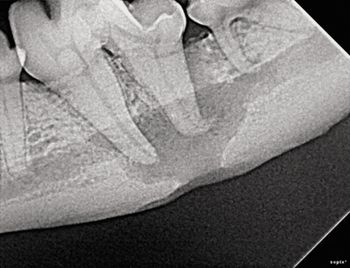

Amplify your dental records with complete dental charting that labels the condition of each tooth. Photographs, full mouth intraoral radiographs and consistent terminology will help you stay in tune when you need to make dental referrals.

Scan the photos, spot the answer and save the patient.

Extraction isn't always the best choice for veterinary patients with tooth troubles. Find out in which cases tooth repair-not removal-can restore dental health.

When is dental extraction the treatment of choice? Find out in this first installment of a multipart series on what to do to when faced with dental pathology.